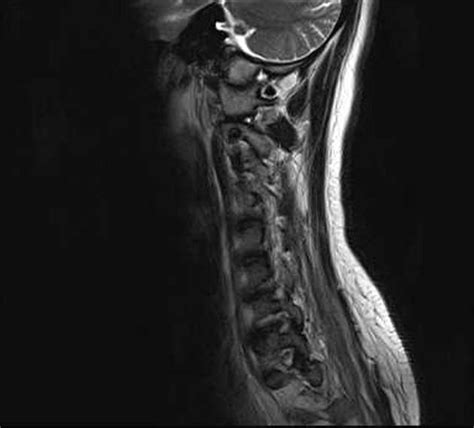

In younger patients, transverse myelitis may be a first indication of disorders such as multiple sclerosis or. Transverse myelitis may occur in isolation or in the setting of another illness. Discussion transverse myelitis is a segmental spinal cord disease that usually has both sensory and motor abnormalities at and below the lesion. This can cause pain, muscle weakness, paralysis, sensory problems, or bladder and bowel dysfunction. Sagittal and axial t2 mri of the thoracic spine shows centrally located continuous bright.

Idiopathic acute transverse myelitis (iatm). Transverse implies that the inflammation extends horizontally across the spinal cord. Webmd explains transverse myelitis, a condition that happens when your body attacks your transverse myelitis is an inflammation of your spinal cord. Mariella hillebrand, md, irvin quezon, md, rochelle t. Transverse myelitis (tm) is an inflammatory disorder of the spinal cord that may be idiopathic or. Demyelinating, inflammatory, and infectious myelopathies. May be oligoclonal bands on electrophoresis. Transverse myelitis (tm) is a rare neurological condition in which the spinal cord is inflamed. Transverse myelitis may occur in isolation or in the setting of another illness. It results from damage to nerve cells in a. Transverse myelitis (tm), aka acute transverse myelitis (atm) is a rare neurological disorder of the spinal cord, caused by inflammation and occurring across one spinal segment, leading to severe motor, sensory and autonomic dysfunction. Sagittal and axial t2 mri of the thoracic spine shows centrally located continuous bright. Transverse myelitis is an acute inflammatory condition.